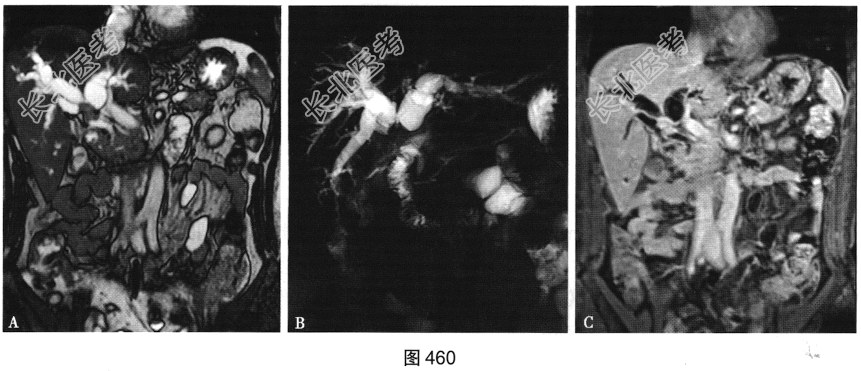

- 多项选择题4.[提示]患者行MRI检查,如图460所示。患者目前最可能的诊断是( )

A、胆囊癌

B、胆囊炎

C、肝内胆管结石

D、胆管炎

E、肝脓肿

F、胆囊结石

G、胆总管癌

H、肝门胆管癌

I、肝外胆管结石

J、肝总管癌